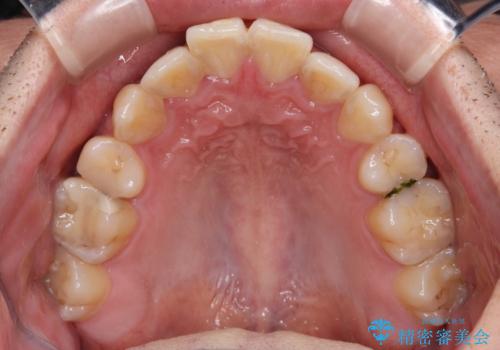

- 高校生の時に行った抜歯矯正の後戻りを気にして来院された患者様です。

インビザラインでの治療を希望されていて、デコボコの程度が中等度であり、安価なパッケージにて対応可能と判断されたため、インビザライン・モデレートを用いて矯正治療を行うこととしました。

インビザライン・モデレートは、製作できるアライナーの枚数に制限があるため、移動可能な量に限りがあるものの、インビザライン・ライトよりも枚数が多いため、幅広い症例に対応可能です。